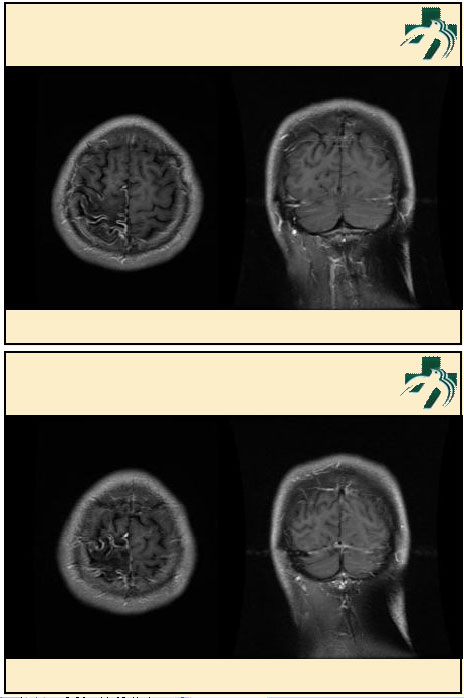

奴卡氏菌感染

第九期三博

读片会

病例之四

北京协和医院 提供

男性,22岁。自觉虫咬后皮疹、肢体麻木4月